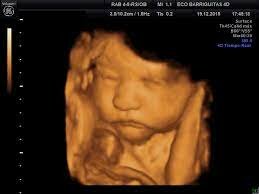

Ecografía bidimensional

Fue cuando la ecografía bidimensional, como un gran hito, se incorporó regularmente en el uso clínico en el sector privado y muy pronto en el sector público, generalizándose en esta área en la década de 1980. Es con este hecho, cuando el feto dejó de ser tan imaginario para la madre como para el médico tratante. Hoy en día, es mucho más cercano con la ecografía tridimensional

En los últimos 30 a 40 años, las interrogantes de siempre de la madre con relación a su feto, han tenido mejores respuestas gracias al progreso del conocimiento, ciencia y tecnología. El perfeccionamiento de lo ya conocido como la ecografía 3D, permitirán una mejor visualización del fenotipo fetal